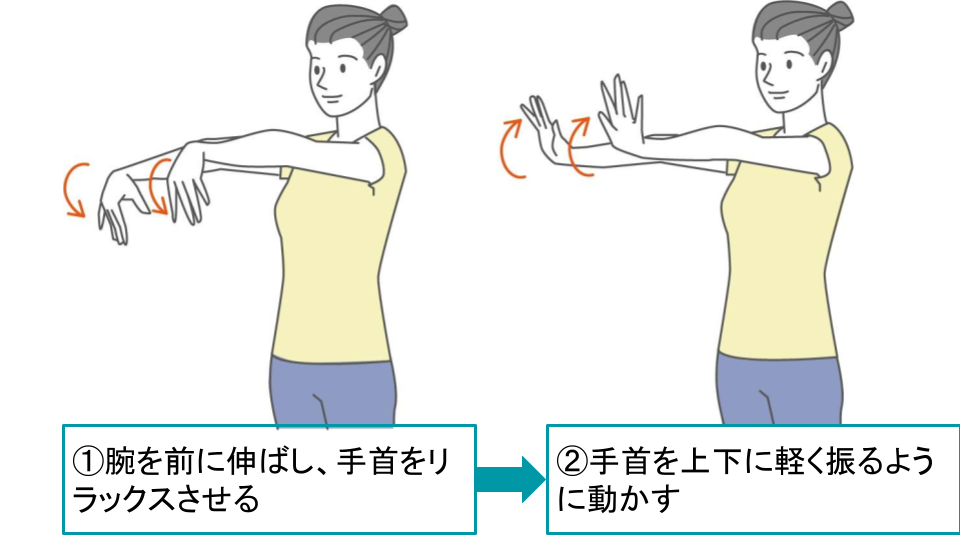

3-2.痛みを緩和させるためのストレッチ

手首や前腕の筋肉を柔らかくするためのストレッチを行うことで、肘の痛みの緩和が見込めます。

これらの筋肉が硬くなると、肘への負担が大きくなり、痛みが出やすくなるからです。

これから紹介するストレッチは、どれも簡単で、場所を選ばずにできます。整形外科での治療と並行して、あるいは、病院で具体的な治療を受けていない場合に、ぜひ試してみてください。

ただし、無理は禁物です!痛みを感じたらすぐに中止し、気持ち良いと感じる範囲で行いましょう。

■肘のストレッチ

■手首の伸展ストレッチ

■手首の屈曲ストレッチ |

いずれのストレッチも難しくはありませんが、以下のようなポイントを押さえておきましょう。

呼吸を止めない(ゆっくりと呼吸しながら行う)

反動をつけない(勢いをつけて行うと、筋肉を傷める可能性がある)

毎日続ける(1日に3〜4回、継続して行う)

痛みがある場合は中止(無理に行うと、症状が悪化する可能性がある)

ストレッチは、肘の痛みを和らげるのに役立ちますが、1回行っただけで劇的に痛みが消えるわけではありませんし、ストレッチだけで痛みが完全に治るわけでもありません。

毎日コツコツと続けることで、少しずつ痛みが和らいでいくことを目指しましょう。